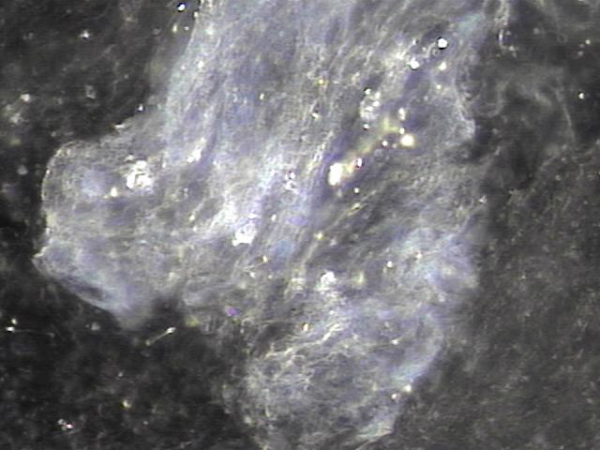

내원 첫날 전립선의 표적 치료후 치료된 정낭의 혈정액과 정자들과 염증들의 현미경학적 자료입니다.

This is a microscopic image taken after your first targeted prostate treatment, showing improvement in the seminal vesicle.

The blood-tinged fluid (hematospermia), sperm, and inflammatory cells have been successfully treated.